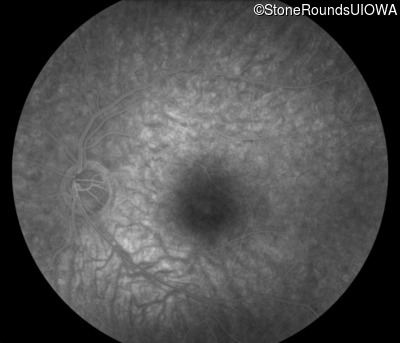

Infrared Fundus Photograph - Right - 20/20 -1

Exemplar